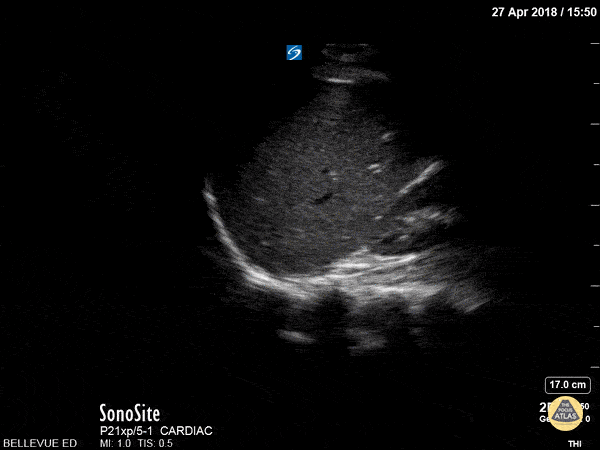

This is a view of the pleural space in the right upper quadrant. We see the isoechoic liver in the center of the screen and the superior pole of the kidney to the right. The superior edge of the liver is flush against the hyperechoic diaphragm. Deep to all of this we see the sinuate hyperechoic vertebrae of the spine. Note that the spine appears to stop at the level of the diaphragm – this is due to the fact that US waves do not transmit through the air-filled lungs, and is a normal finding. If the spine did extend beyond the diaphragm (“spine sign”) that would suggest the presence of an effusion. The area above the diaphragm which comes into view when the patient inhales is the same echotexture as the liver (“mirror image artifact”), further indicating that there is only air above the diaphragm and not effusion or consolidation. Hannah Kopinksi and Dr. Lindsay Davis - NYU Emergency Medicine